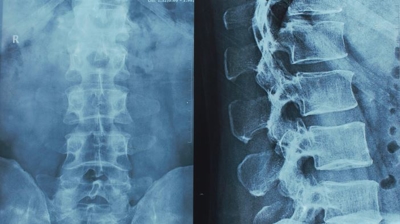

Car accidents often lead to spinal damage because your body is banged about in a crash, and these sudden blows damage the spinal cord and the sensitive tissues around it, like discs, vertebrae, and ligaments. Depending on the speed and final resting place of a vehicle post-crash, a spinal cord could be severed, crushed, or dislocated. Car accidents are variable incidents, and they don’t always end the same way, even when the conditions are similar. Spinal cord damage in one high-velocity crash can be minor, but a similar crash could just as easily create irreparable damage to the spinal cord and nervous system. The intensity of the trauma experienced in a car crash and the way a body impacts its surroundings will be the ultimate determining factor in a spinal injury.

A spinal cord is a bundle of cylindrical nervous tissues housed in a long bone. The long bone is the vertebrae, and it is an extremely sensitive body part that, when damaged, can leave lasting trauma. Car accidents commonly result in spinal injuries. From the cord to the bone to the disc, spinal injuries cause victims to experience long periods of severe pain and suffering.